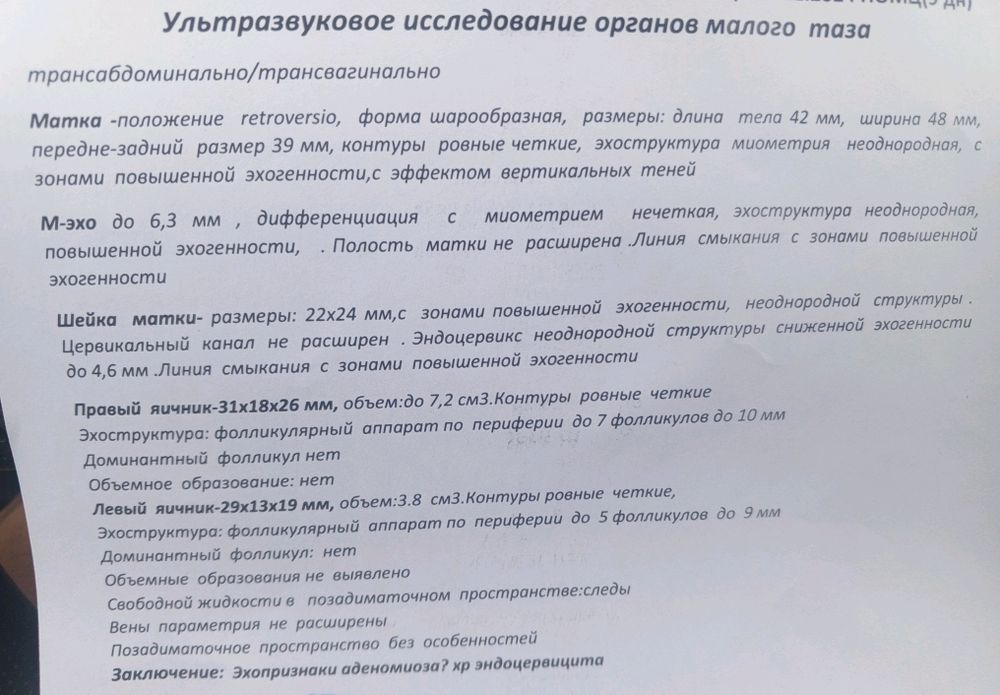

Жанна, 😁мда... Узист хороший, но запись у неё плотная, за три дня девала узи сказали что жидкость есть и то что и в пя и в ля как будто что-то формируется и не видно фолликул, написала что по одному фоллекулу хотя в начале циклов всегда 6-7 шт и посоветовали через пару дней прийти но пришли 🩸

Жанна, сходила, вроде не беременная, но что то странное, она хороший доктор но почему то во вторую фазу у неё всегда тонкий эндометрий когда у других пышный... И образование в правом на фото как то больше выглядит, да и яйчник большой для начала цикла, он такой где-то ближе к концу... Если найду старые заключение где ближе концу тоже эндометрий был тонкий.

матка увеличиная и воспаление...

матка увеличиная и воспаление...

матка увеличиная и воспаление...

матка увеличиная и воспаление...

Светлана , что-то действительно странное ((

Нужно ещё одно мнение мне кажется((